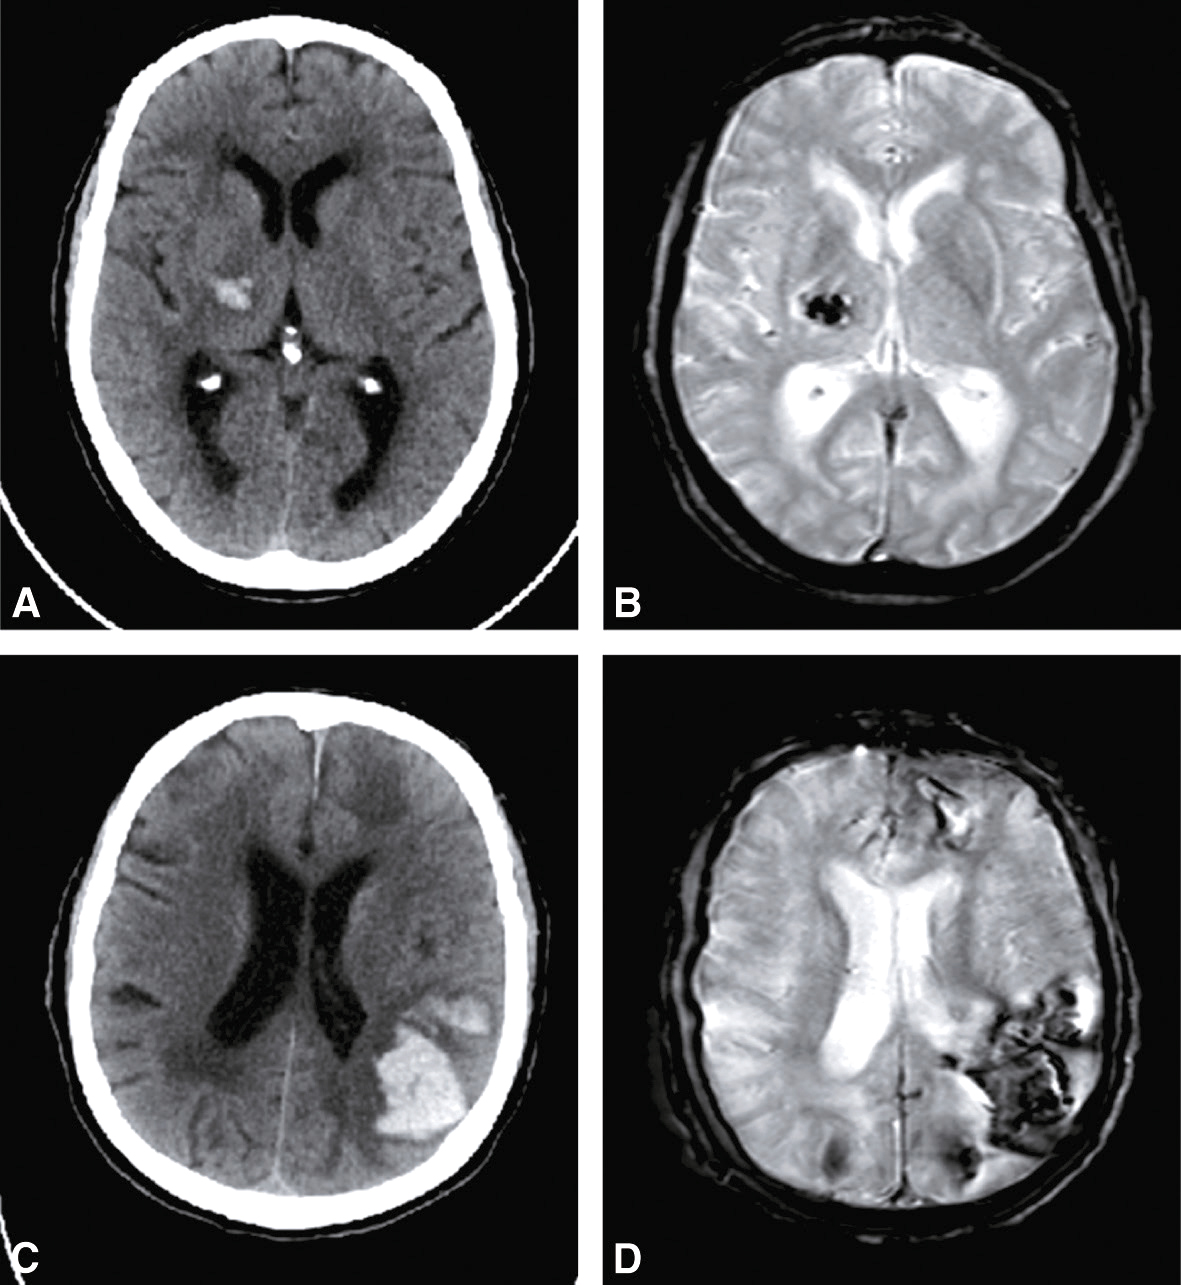

• Figure thrombose veineuse cérébrale (fig. 28.10);

Fig. 28.10 Figure Thrombose veineuse cérébrale.

A. Thrombose du sinus latéral gauche en scanner sans injection. B. Infarctus veineux hémorragique en scanner. C. Infarctus veineux en séquence IRM FLAIR. D. Infarctus veineux avec remaniement hémorragique en séquence IRM T2*. E. Infarctus veineux avec remaniement hémorragique en séquence IRM diffusion. F. Thrombose du sinus latéral gauche en séquence IRM T1 après injection de gadolinium.

• • endocardite infectieuse (rupture d’anévrisme mycotique);

• • artérites cérébrales;

• • méningo-encéphalite herpétique.